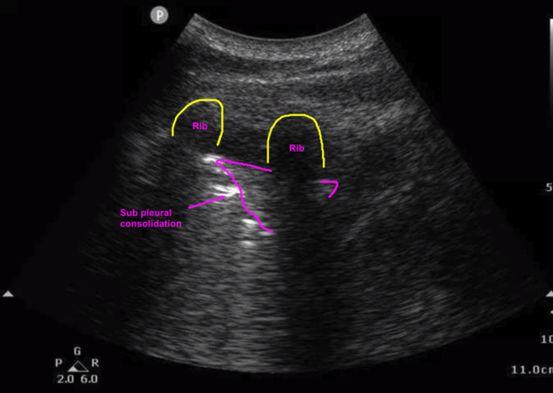

B. Lung (Fig 5)

The thoracic ultrasound is not the single best imaging modality especially if used alone. However, if abnormal or when used in conjunction with the cardiac or lower extremity (LE) venous ultrasound, the lung ultrasound may be extremely helpful. The association of a normal (A-profile) lung POCUS with a positive LE venous scan has been shown to favor the diagnosis of PE. Recently, several lung abnormalities have been described for PE, including the (1) presence of multiple lesions, (2) rounded, polygonal or wedge shaped lesions, (3)

Fig. 5: Normal lung and sub-pleural consolidation

Normal lung

Sub-pleural consolidation

associated pleural effusions, (4) right lung affectation more than left, (5) and posterior lower lung findings. In patients presenting with dyspnea, thoracic ultrasound can help rule out other etiologies of respiratory distress such as pneumonia, pulmonary edema, pneumothorax, or COPD/asthma.

Sub-pleural consolidations Thoracic ultrasound seeks to evaluate the pleural line for subpleural consolidations that may be representative of pulmonary infarction. The majority of findings occur in the posterior and inferior areas of the lung. Some studies suggest that pleural lesions between 0.5cm to 3cm are more indicative of PE.